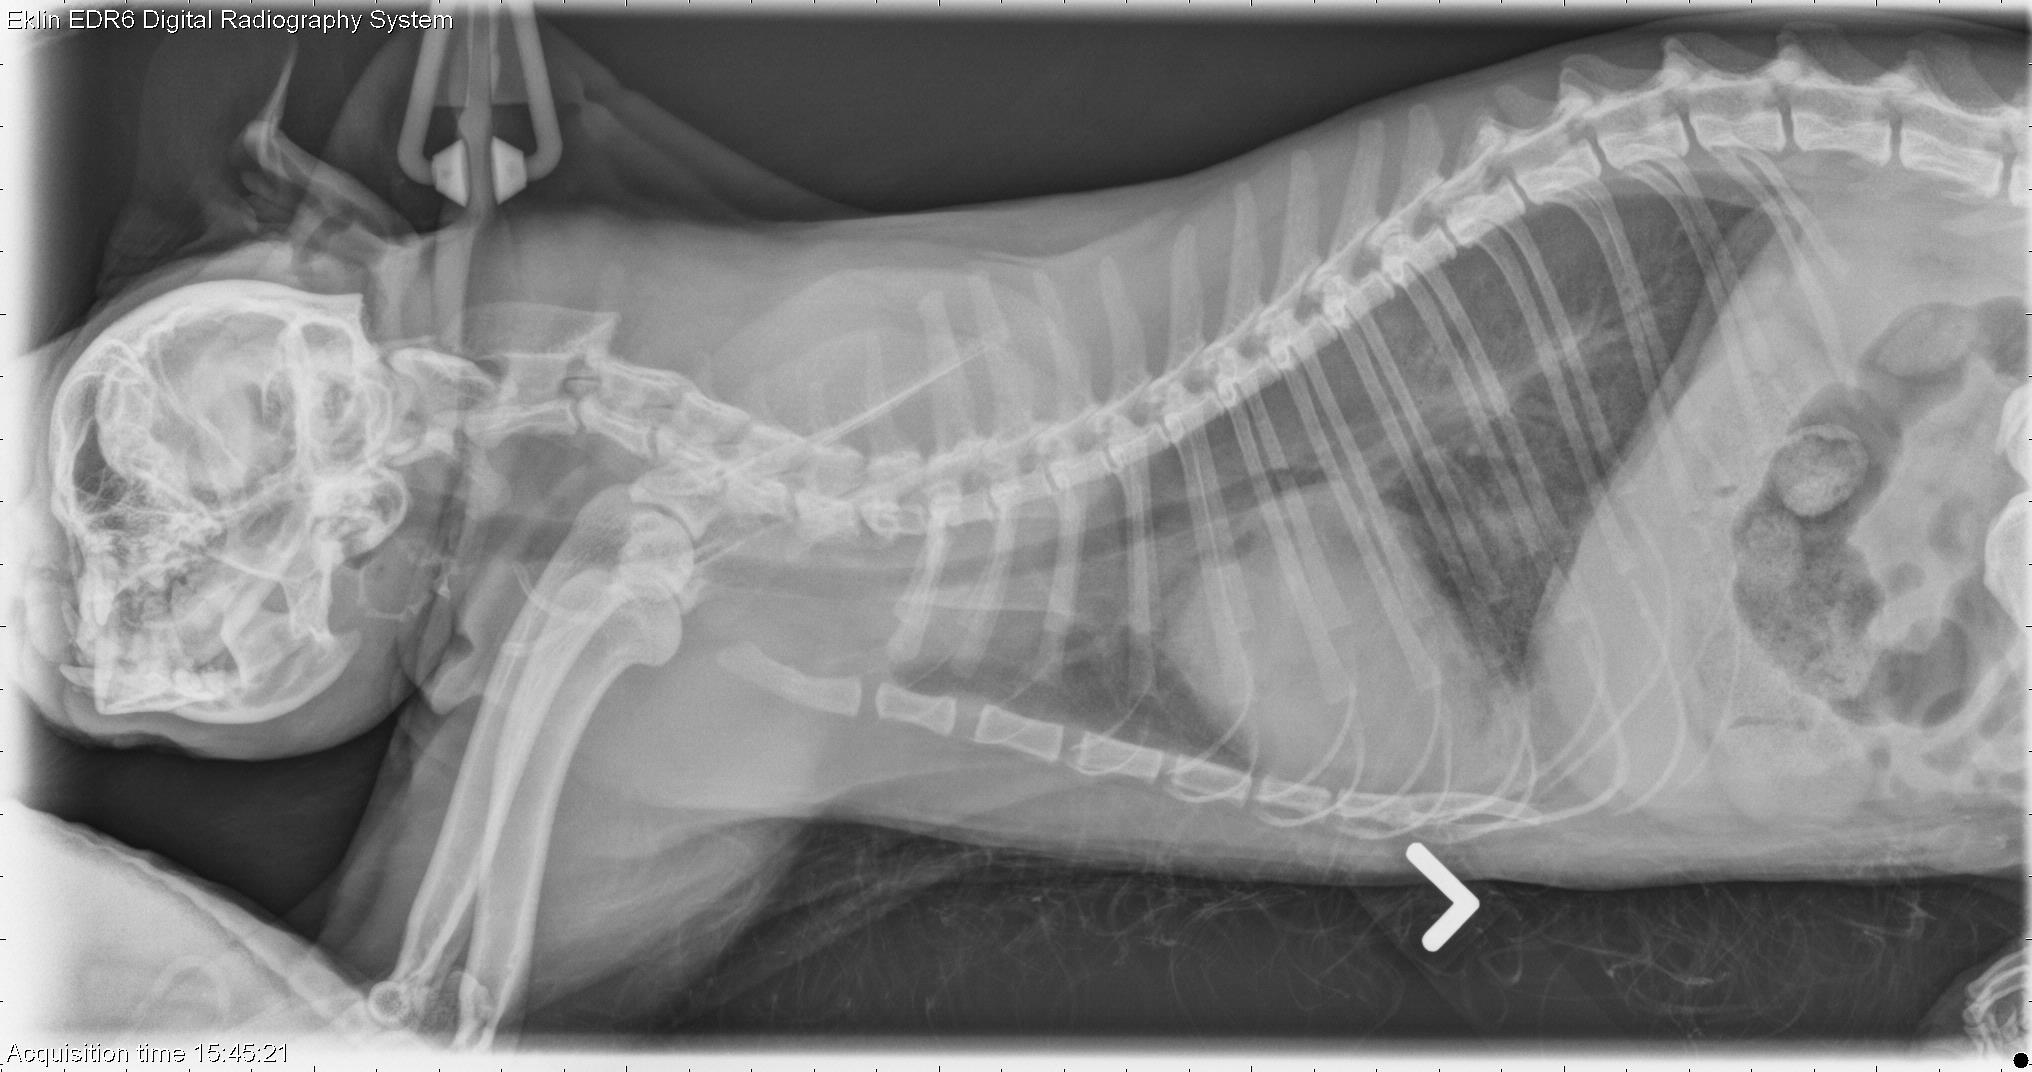

This week’s case is a 5-year-old male neutered Persian cat with increased respiratory rate and effort. What are your findings?

R LAT Thorax

The cardiac silhouette is enlarged and rounded, occupying the entire thoracic width on the dorsoventral projection. The pulmonary vasculature is enlarged. There is a diffuse interstitial pattern throughout the lungs that is beginning to obscure the cardiac silhouette and vasculature. No other abnormalities are identified.

• Cardiomegaly with heart failure and pulmonary edema

• The cardiomegaly is most likely due to cardiomyopathy

• Hypertrophic cardiomyopathy as well as pericardial effusion were confirmed on echocardiography.